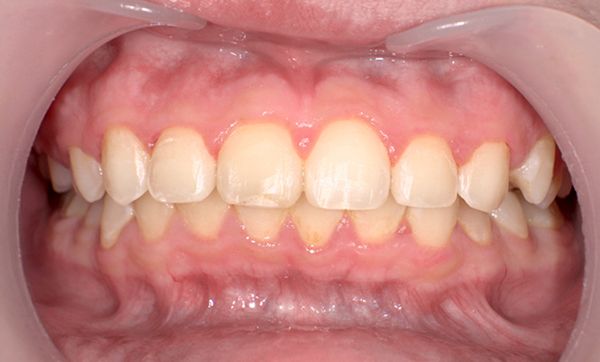

| 治療前 | 治療後 |

|---|---|

|